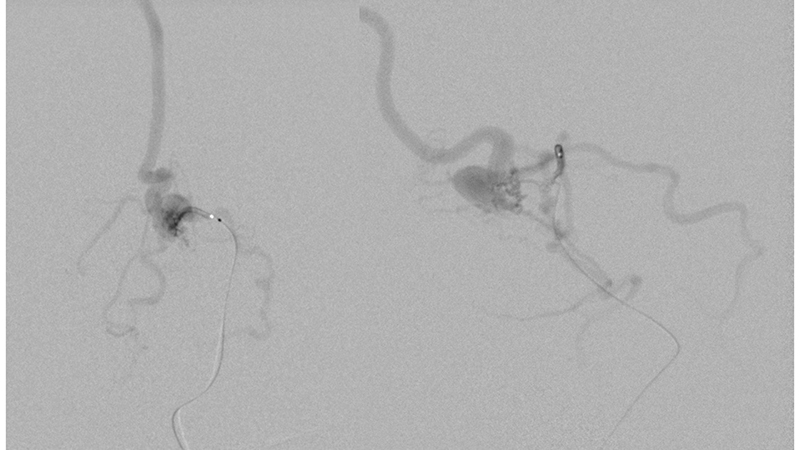

Ως αποτέλεσμα της ανωτέρω αιμοδυναμικής μεταβολής και με δεδομένη την ιακνοποιητική κλινική βελτίωση, αποφασίσθηκε να μην γίνει επέμβαση και ο ασθενής να τεθεί υπό χαμηλού μοριακού βάρους ηπαρίνη λόγω της θρομβώσεως των οπισθίων φλεβωδών κόλπων. - Δύο χρόνια αργότερα, υπερεκλεκτικός καθετηριασμός υποεπενδυματικών και χοριοειδών τροφοφόρων κλάδων από το Ρ1, Ρ2 και Ρ3 των οπισθίων εγκεφαλικών αρτηριών.

- Υπερεκλεκτικός καθετηριασμός υποεπενδυματικών και χοριοειδών τροφοφόρων κλάδων από το Ρ1, Ρ2 και Ρ3 των οπισθίων εγκεφαλικών αρτηριών.

- Τελική αγγειογραφία επανελέγχου του σπονδυλοβασικού μετά την δεύτερη συνεδρία εμβολισμού. Παραμένουν δύο με τρεις μικροί τροφοφόροι αρτηριακοί θαλαμοδιατιτραίνοντες κλάδοι από το Ρ1 τμήμα της αριστερής οπίσθιας εγκεφαλικής αρτηρίας, που λόγω του πολύ μικρού νεγέθους των θα αντιμετωπισθούν μετά από 2 έτη. Η φλεβική παροχέτευση γίνεται προς την φλέβα του Γαληνού, και διά μέσου επιπολής φλεβός προς την έσω επιφάνεια του αριστερού βρεγματικού λοβού προς τον άνω οβελιαίο κόλπο. Οι εγκάρσιοι κόλποι και ο Ληνός έχουν επανασηραγγοποιηθεί.

- Παρατηρείται πλήρης αποσυμφόρηση του περιμεσεγκεφαλικού φλεβικού δικτύου με σημαντική ελάττωση της φλεβικής συμφορήσεως περιμεσεγκεφαλικά καθώς και προς τον νωτιαίο μυελό.